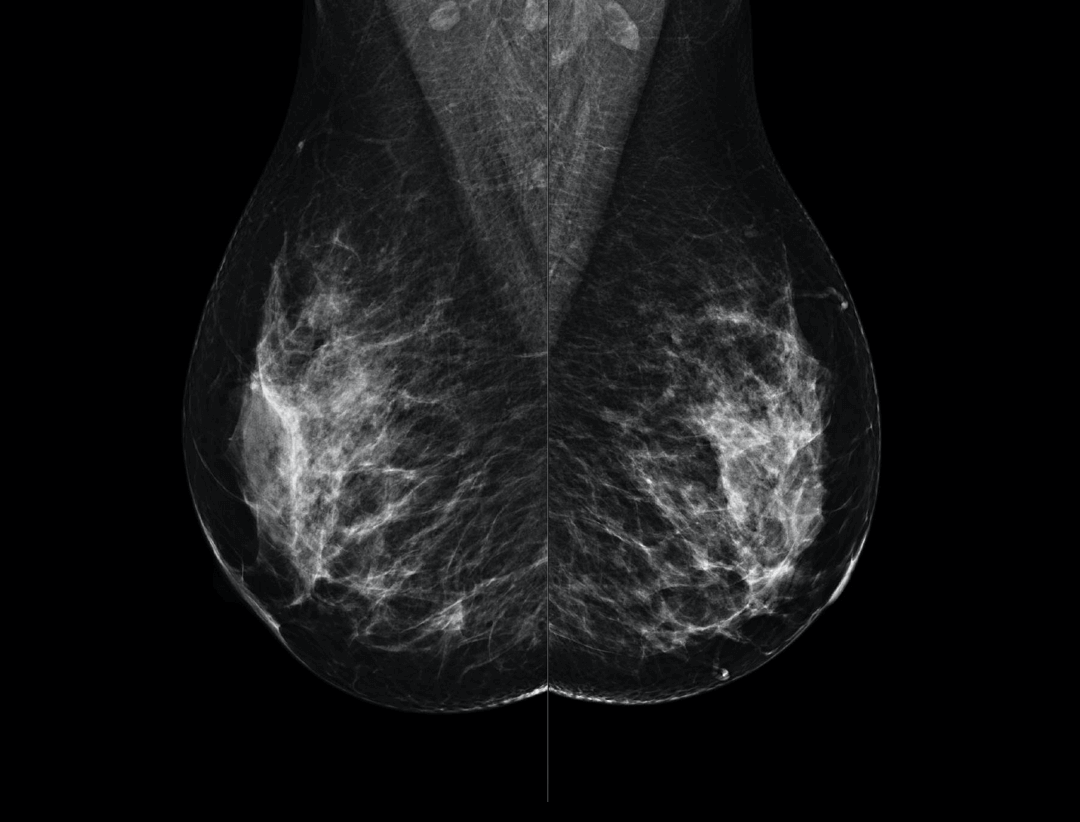

Large coverage amorphous-silicon (a-Si) flat panel detector featuring an optimized active matrix array provides high spatial resolution and high image acquisition speed at a lower dose.

High performance tungsten target X-ray tube offers high resolution image for both dense and fatty breast densities.

Intelligntly detects breast density and thickness, then auto selects the appropriate filter combination.